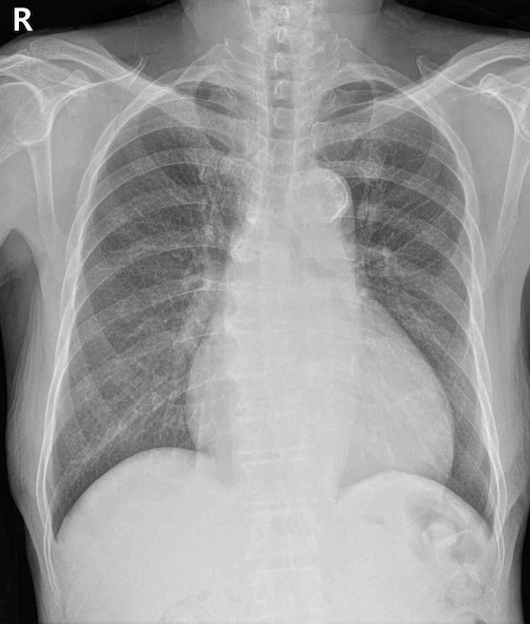

69세 남자가 6개월 전부터 숨이 차서 병원에 왔다. 평지에서 걷는 데는 지장이 없으나 계단으로 한 층을 오르면 쉬어야 할 정도라고 한다. 혈압 130/80 mmHg, 맥박 68회/분, 호흡 16회/분, 체온 36.1°C이다. 복장뼈 오른쪽 2번째 갈비사이공간에서 3/6도의 수축기 심잡음이 들리고, 오른쪽 경동맥에서 수축기 잡음이 들린다. 가슴 X선사진과 심전도이다. 진단은?

CXR: Cardiomegaly

• CXR에서는 cardiomegaly, ECG에서는 V4~6의 amplitude가 겹칠 정도로 높아진 left ventricular hypertrophy(LVH)가 확인된다.